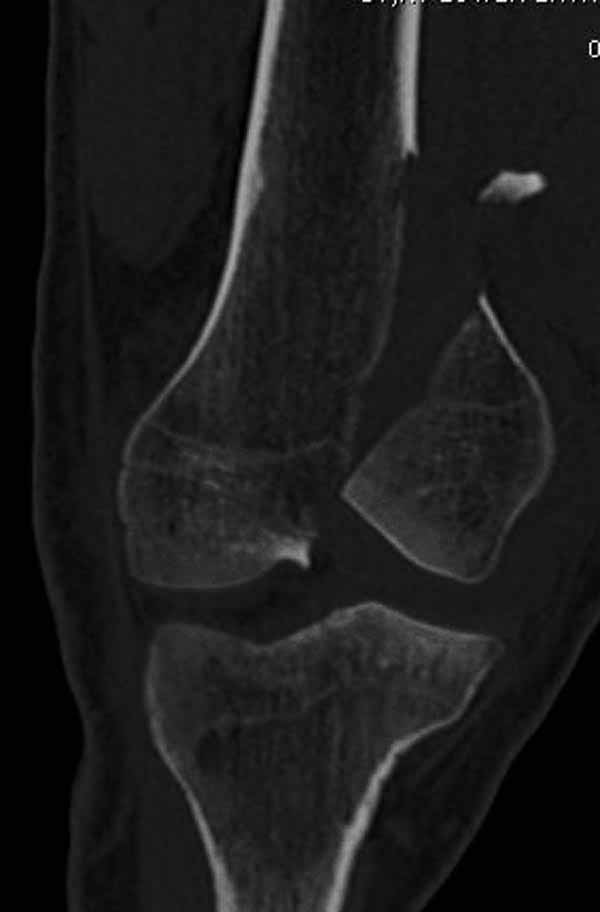

>Сразу не обратил ваше внимание именно на это, что сломаны оба мыщелка, и больший является именно медиальным мыщелком

А теперь по поводу лечения перелома. Среди всех чрез/меж-мыщелковых переломов в 38% сопровождются переломом в корональной плоскости, т.е перелом Hoffa. Nork et al, J Orthop Trauma, 87:564, 2005.

У больных как в этом случае, с вовлечением двух мыщелков правильно, что сделали вытяжение до операции. Здесь имеется флексионный компонент на другой стороне, и я бы рекомендовал операцию делать из двух доступов. Сперва фиксировать медиальную колонну custom made пластиной, обычно 1/3 тубулярной пластиной в 4.5 мм, потому что пока производители опаздывают с медиальной пластиной.

Пластину надо устанавливать на апексе перелома, иначе фрагмент начнет сползать. А на второй стороне, если имеется большой одиночный фрагмент тогда проблем не бывает, и их можно собрать компрессирующими винтами. Проблема наступает тогда когда многофрагментраность на латеральной стороне, где надо применить комбинированный метод, иногда несколькими пластинами. Или сменой позиции установки пластины, чтобы максимально прикрыть перелом и создать боковую поддержку.